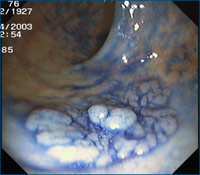

Magenspiegelung mit Kontrastverstärkung im Bereich der unteren Speiseröhre bei Verdacht auf Barrett-Syndrom mit Narrow Band Imaging (NBI). Durch einen speziellen Filter kann die Kontrastierung bei der Betrachtung im Bereich der unteren Speiseröhre so angehoben werden, dass geringe Veränderung der Schleimhaut in der Endoskopie erkannt und durch gezielte Gewebeprobenentnahmen weiter differenziert werden können.

Durch Aufsprühen von Färbemitteln (Methylenblau (Speiseröhre) und Indigokarmin (Darm)) werden Veränderungen in Magen, Speiseröhre und Darm bei der Spiegelung besser erkannt.